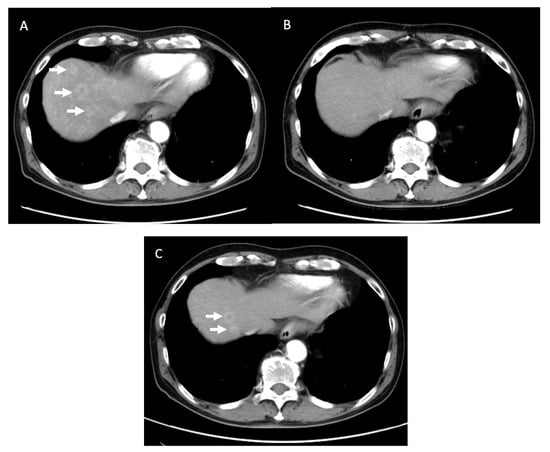

| Patient No. | Adjuvant Chemotherapy | Recurrence Site/Time to Recurrence from CS (Month) | Final Outcome | OS (Months) from Initial Treatment [from Surgery] |

|---|---|---|---|---|

| 1 | mFX | Liver/8.5 | Death | 24.9 [17.7] |

| 2 | S1 | Remnant pancreas/20.1 | Death | 65.9 [57.8] |

| 3 | mFX | No | Alive | 40.9 [16.7] |

| 4 | mFX | No | Alive | 35.2 [12.0] |

| 5 | mFX | No | Alive | 26.1 [19.3] |

| 6 | No | No | Alive | 27.3 [13.9] |

| 7 | S1 | Lung/24.1 | Death | 35.1 [30.6] |

| 8 | S1 | No | Alive | 26.7 [12.6] |